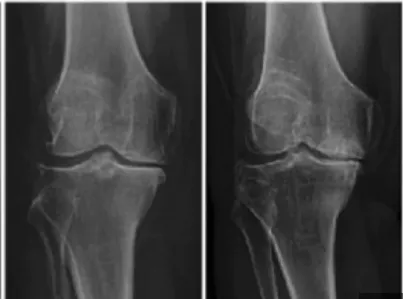

무릎 관절염은 많은 사람들에게 영향을 미치는 흔한 관절 문제 중 하나입니다. 이러한 질환이 있는 환자들은 적절한 운동을 통해 무릎 관절을 더욱 강화하고 통증을 완화하는데 도움을 줄 수 있습니다. 이 글에서는 무릎 관절염에 좋은 운동 10가지 및 주의사항에 대해서 자세히 살펴보겠습니다.

무릎 관절염은 일상생활에 불편을 초래할 수 있지만 적절한 운동과 주의 사항을 준수하면 증상을 개선하고 생활의 질을 향상할 수 있습니다.

위에서 소개한 무릎 관절에 좋은 운동은 무릎 관절을 강화하고 통증을 완화하는데 도움을 주는 것뿐만 아니라, 제대로 수행하면 다른 건강 이점도 얻을 수 있습니다.